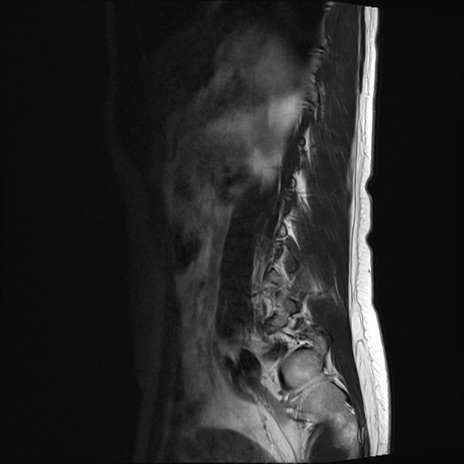

腰椎MRI

STIR(矢状断像)